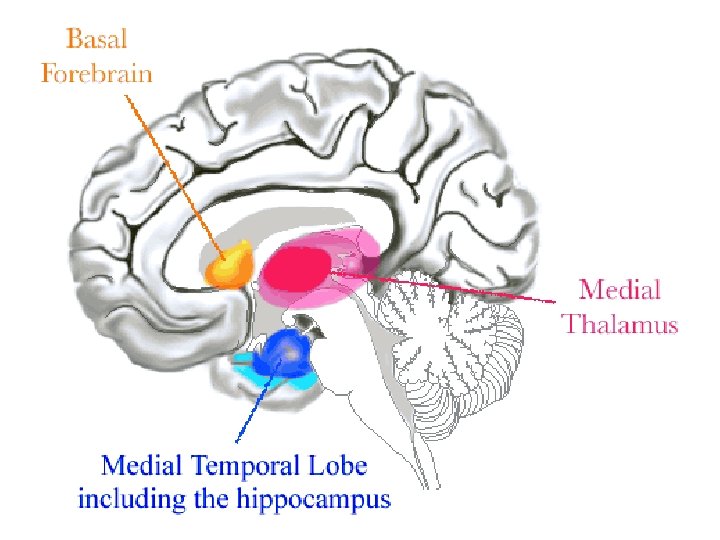

Integrated Circuitry Linking Temporal, Diencephalic, and Basal Forebrain Regions

Two Limbic Circuits Anterior Thalamus Cingulate Gyrus Dorsomedial Thalamus Mamillothalamic Tract Mammilary Bodies Fornix Hippocampus Medial (Papez) Orbitofrontal Amygdalofugal pathways Uncus Amygdala Lateral

Two Limbic Circuits and the Two-system theory of amnesia Anterior Thalamus Cingulate Gyrus Dorsomedial Thalamus Mamillothalamic Tract Mammilary Bodies Orbitofrontal Amygdalofugal pathways Fornix Uncus Hippocampus Amygdala PRPH Medial (Papez) Lateral

Basal Forebrain Anatomy